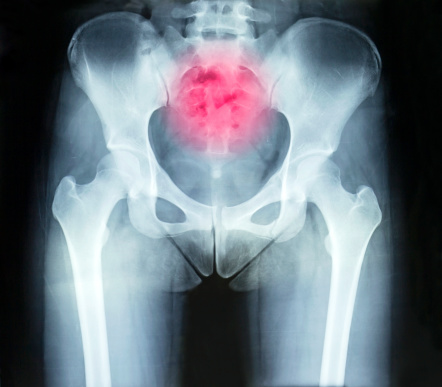

These Daily Habits Can Help Ease Joint Pain

How you go about your day-to-day life can affect whether or not you experience joint pain. In order to ease and prevent joint pain as much as possible, there are some daily habits you can perform that are detailed below. Daily Habits to Prevent Joint Pain Eat breakfast at home: Eating breakfast out or on ...click here to read more